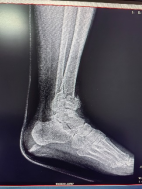

患者56歲男性,外傷致左踝部疼痛出血、腫脹畸形、活動受限,X線片顯示左脛腓骨遠端碎折,骨折斷端嵌插,骨折波及關(guān)節(jié)面,左脛骨近端內(nèi)側(cè)骨質(zhì)連續(xù)性中斷。